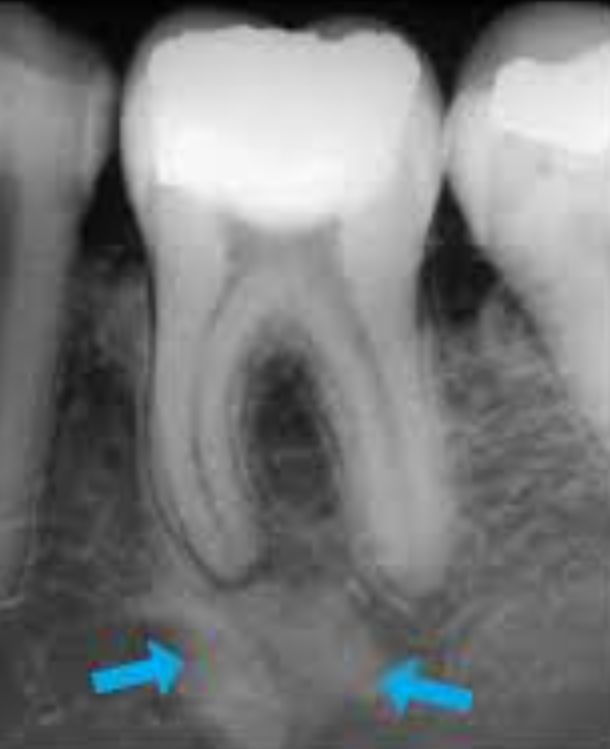

Examen radiographique

- Début : image radioclaire faible en « croissant de lune » au tiers apical

- Extension : image arrondie ou ovalaire, contours diffus, centre radioclaire, effacement de la trabéculation osseuse

- Persistance : destruction radiculaire (aspect « sucé »), destruction centrifuge de l’os alvéolaire

Piège diagnostique : Éviter la confusion avec des structures anatomiques normales : trou mentonnier, fossette incisive, canaux accessoires.

Diagnostic positif — Les 4 signes clés à retenir

- Absence de réponse aux tests de vitalité

- Rougeur en regard de l’apex

- Choc en retour à la percussion transversale

- Image radioclaire < 5 mm, contours diffus